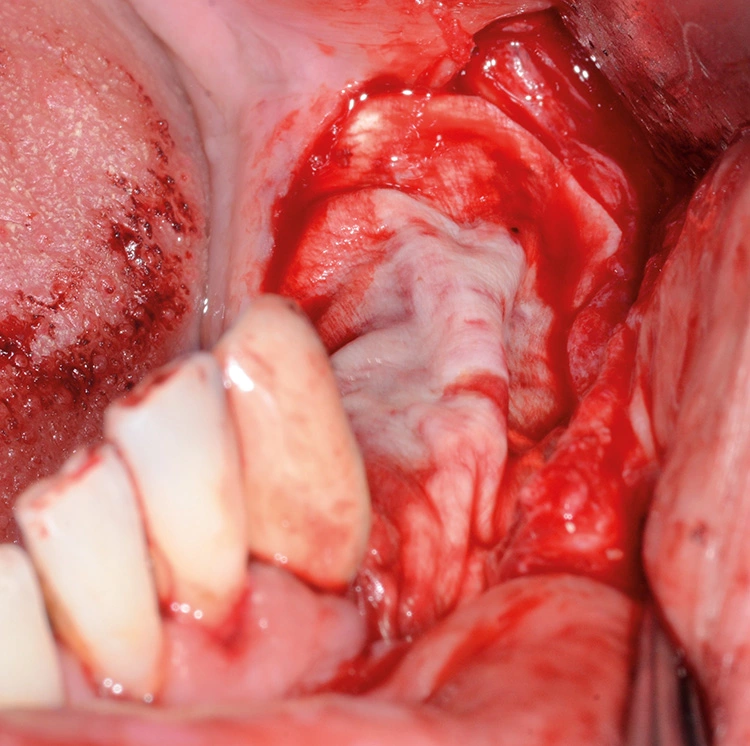

Implantation: 7 Monate nach Augmentation

Trotz der schlechten, hart- und weichgewebigen Grundvoraussetzungen konnte der Kieferkamm zufriedenstellend rekonstruiert werden. Die Augmentation des kombinierten, horizontalen und vertikalen Defekts mit Yxoss CBR®, Geistlich Bio-Oss®, Geistlich Bio-Gide®, autologem Knochen und PRF ermöglichte die Implantation mit hoher Primärstabilität in den rekonstruierten Bereich.